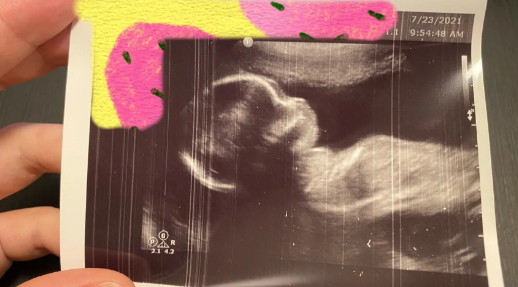

胎儿性别测试杯是2006年美国科学家研制的,检测原理是通过分离人体内激素与专门的化学物质接触后发生的反应来进行,将孕妇尿液装入杯中后的有没有变色来进行男女辨别。

美国胎儿测试杯使用简单,结果也比较好看,盛入尿液10分钟后,可以观察测试杯中的颜色变化,绿色为男孩,橙色为女孩。